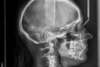

Traitement par gouttières et chirurgie

Début de traitement